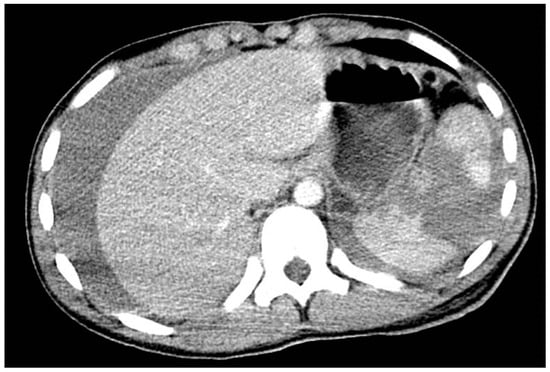

- Zakaria, O.M.; Daoud, M.Y.I.; Zakaria, H.M.; Al Naim, A.; Al Bshr, F.A.; Al Arfaj, H.; Al Abdulqader, A.A.; Al Mulhim, K.N.; Buhalim, M.A.; Al Moslem, A.R.; et al. Management of pediatric blunt abdominal trauma with split liver or spleen injuries: A retrospective study. Pediatr. Surg. Int. 2023, 39, 106. [Google Scholar] [CrossRef]